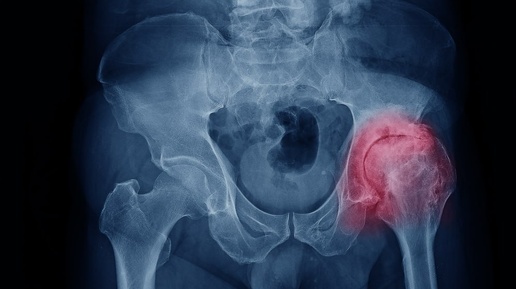

Как справиться с коксартрозом тазобедренного сустава и вернуть себе подвижность

Как справиться с коксартрозом тазобедренного сустава и вернуть себе подвижность 🦵✨ Коксартроз — это заболевание, связанное с износом хряща в тазобедренном суставе, которое может привести к боли, скованности и трудностям при ходьбе. Многие считают, что с таким диагнозом ничего нельзя сделать, но это не так! Даже на поздних стадиях болезни можно значительно улучшить качество жизни и избежать операции, если подойти к лечению грамотно и последовательно. 💪 🔸 Что происходит при коксартрозе? 🤔 Тазобедренный...